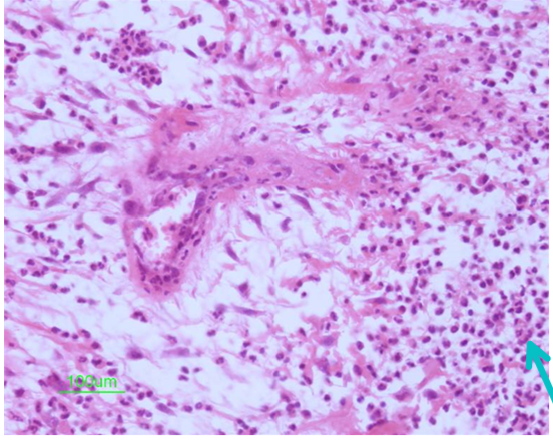

Identify this structure:

loosely arranged fibroblasts